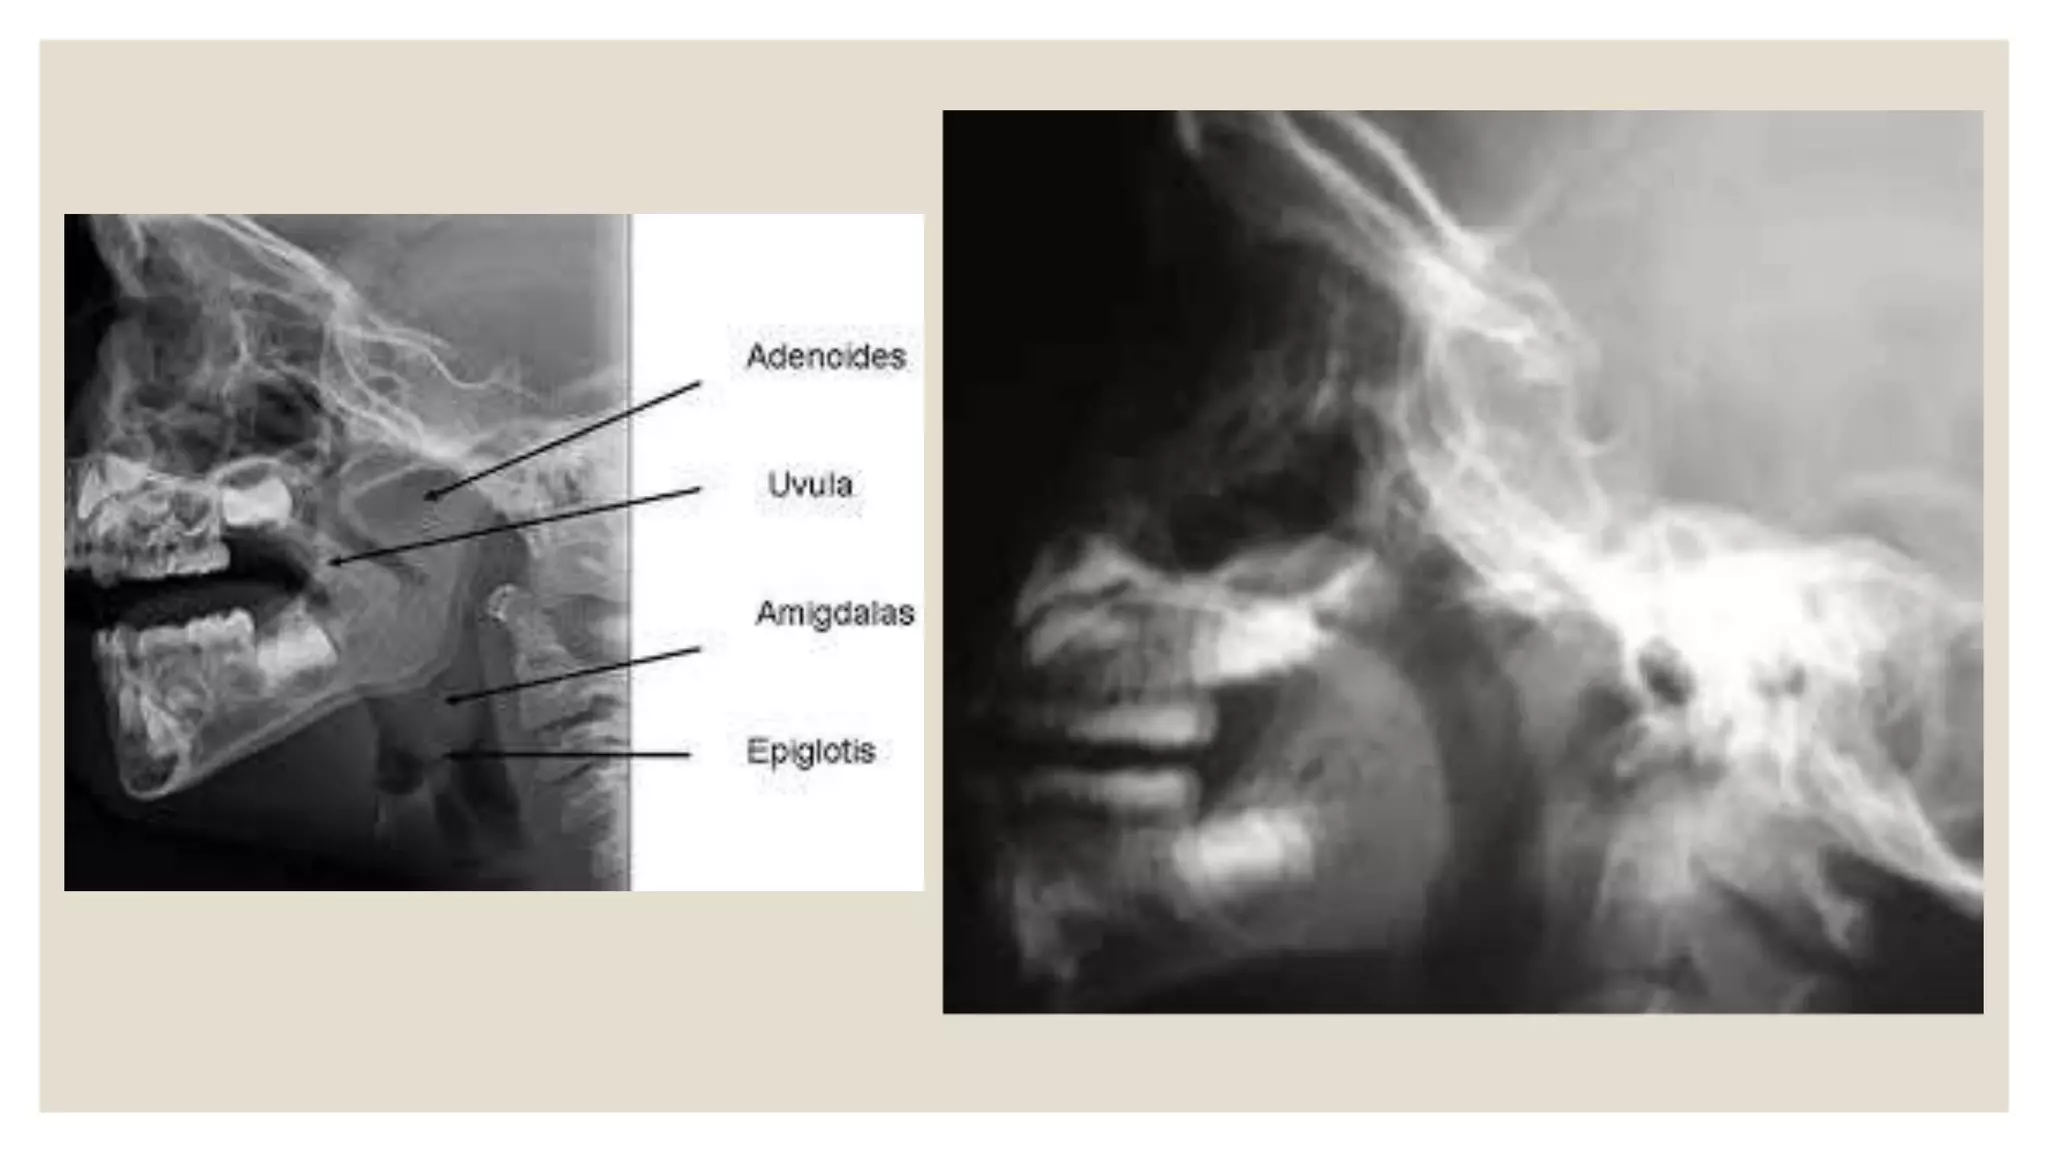

●Radiografía lateral de cavum*

Permite hacer una valoración porcentual de la superficie

que este ocupado por tejido adenoideo

• 24.

●Radiografía lateral decavum* Permite hacer una valoración porcentual de la superficie que este ocupado por tejido adenoideo ●Nasofaringoscopia De gran valor y fiabilidad. Las vegetaciones se pueden ver a través de la nariz (endoscopio rígido o flexible).

• #25 Se debe tomar la Rx a aproximadamente 80 cm del foco, en el niño de pie, cabeza en normoextensión, en perfecta lateralidad, con boca entreabierta y respirando suavemente por esta. Con estas condiciones es entonces fácil ubicar 3 reparos anatómicos: apófisis clinoides anteriores, corona de la última pieza dental emergida y articulación occipitoatloídea. Con estos tres puntos se puede formar un triángulo groseramente isósceles. La bisectriz del ángulo superior del mismo pasa por una zona del rinofarinx de tal manera que nos permite hacer una valoración porcentual de este ocupado por tejido adenoideo